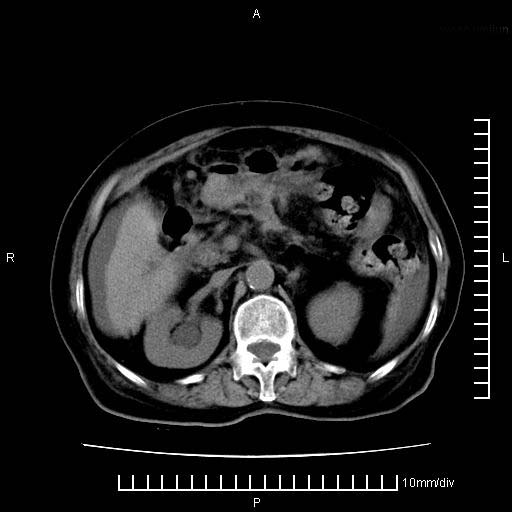

标题: CT28280:腹部增强:女性,80岁

上腹疼痛月余,外院核磁诊断胰腺癌。现临床示右下腹可明显触及包块,可片子上怎么没有看到?

1.胰腺颈体部癌。

胰腺体部癌累及周围器官,腹膜、粘连

1。胰腺ca伴腹膜腔转移

胰腺结构模糊,胰尾部见囊性包块,周围脂肪密度增高,左肾前筋膜增厚,胸水、腹水。不符合胰腺ca伴腹膜腔转移。考虑胰腺炎伴假性囊肿形成、胸腹腔积液。

1)考虑胰腺癌并胰腺假性囊肿形成。2)肝内低密度灶,不排除转移。3)右肾盂积水。4)腹水。5)右侧胸腔积液并右肺下叶部分膨胀不全。